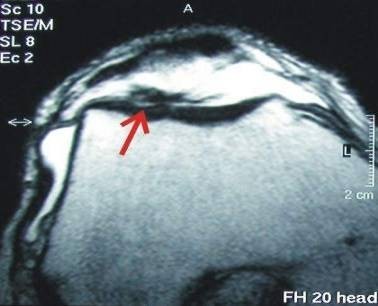

Example of a successful cartilage repair: Full cartilage defect on the patella sliding bearing.

After coverage with a cultivated cartilage, the defect is completely filled and the patient pain-free.